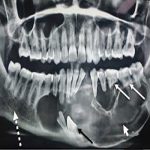

نقش رادیولوژی در تشخیص کیستها و ضایعات فکی